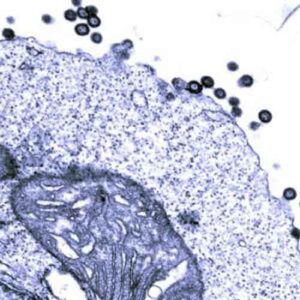

Ricercatori provenienti da Repubblica Ceca e Germania hanno scoperto per la prima volta la dettagliata struttura del guscio che circonda...